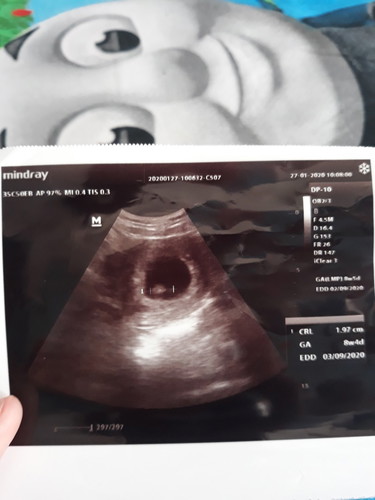

ukuran janin

Wajar gak bun 8w4d ukuran janin segitu?

edd : 03.09.2020 berarti postingan lama bund